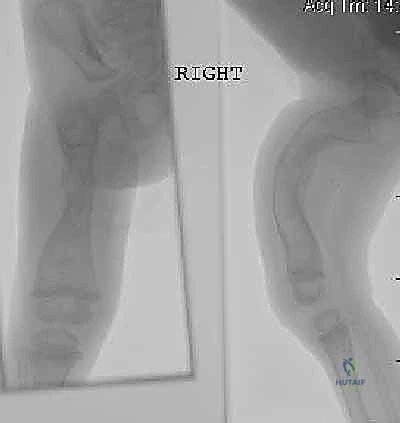

الخطوة الثالثة: بضع العظم المتعدد عبر الجلد (Multiple Percutaneous Osteotomies)

بدلاً من فتح الساق بالكامل، يقوم الدكتور هطيف بعمل ثقوب صغيرة جداً (مليمترات) في الجلد. باستخدام أدوات دقيقة جداً (مثل الإزميل الدقيق أو المثقاب المتخصص)، يتم قطع العظم في أماكن التقوس من الداخل دون إتلاف الأنسجة الرخوة أو العضلات المحيطة. هذا يحافظ على التروية الدموية للعظم (Periosteum)، مما يسرع من التئام العظم بشكل مذهل.

الخطوة الرابعة: إدخال المسمار التلسكوبي

بعد تقويم العظم وجعله مستقيماً كحبات المسبحة على خيط، يتم إدخال السلك الدليلي (Guide Wire). ثم يتم إدخال الجزء الخارجي (الأنثوي) من المسمار التلسكوبي وتثبيته في الجزء العلوي من العظم (Epiphysis).

بعد ذلك، يتم إدخال الجزء الداخلي (الذكري) من المسمار عبر الجزء السفلي من العظم وتثبيته في المشاشة السفلية. هذا التصميم العبقري يضمن حماية العظم بالكامل من الداخل.